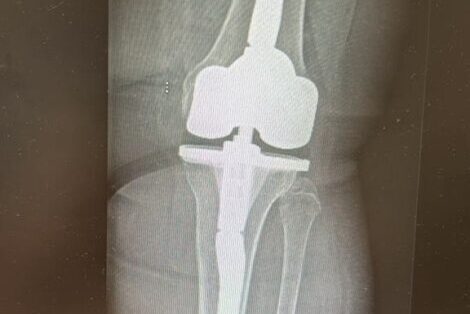

Эндопротезирование коленного сустава — это высокотехнологичная операция, способная кардинально улучшить качество жизни пациентов с тяжелыми поражениями колена. Когда консервативные методы лечения исчерпаны, а боль и ограничение подвижности становятся постоянными спутниками, замена сустава часто становится единственным выходом. В России граждане могут пройти эту дорогостоящую процедуру в рамках программы обязательного медицинского страхования (ОМС) и системы квотирования высокотехнологичной медицинской помощи (ВМП).

Использование качественных современных имплантатов

Клиники, работающие в системе ОМС и ВМП, обязаны использовать только сертифицированные эндопротезы, соответствующие строгим российским и международным стандартам качества и безопасности. Хотя пациент не выбирает конкретную модель протеза самостоятельно (она определяется медицинскими показаниями и протоколами клиники), он может быть уверен, что имплантат обладает необходимыми характеристиками долговечности и функциональности. Производители эндопротезов для государственных программ проходят тщательный отбор.